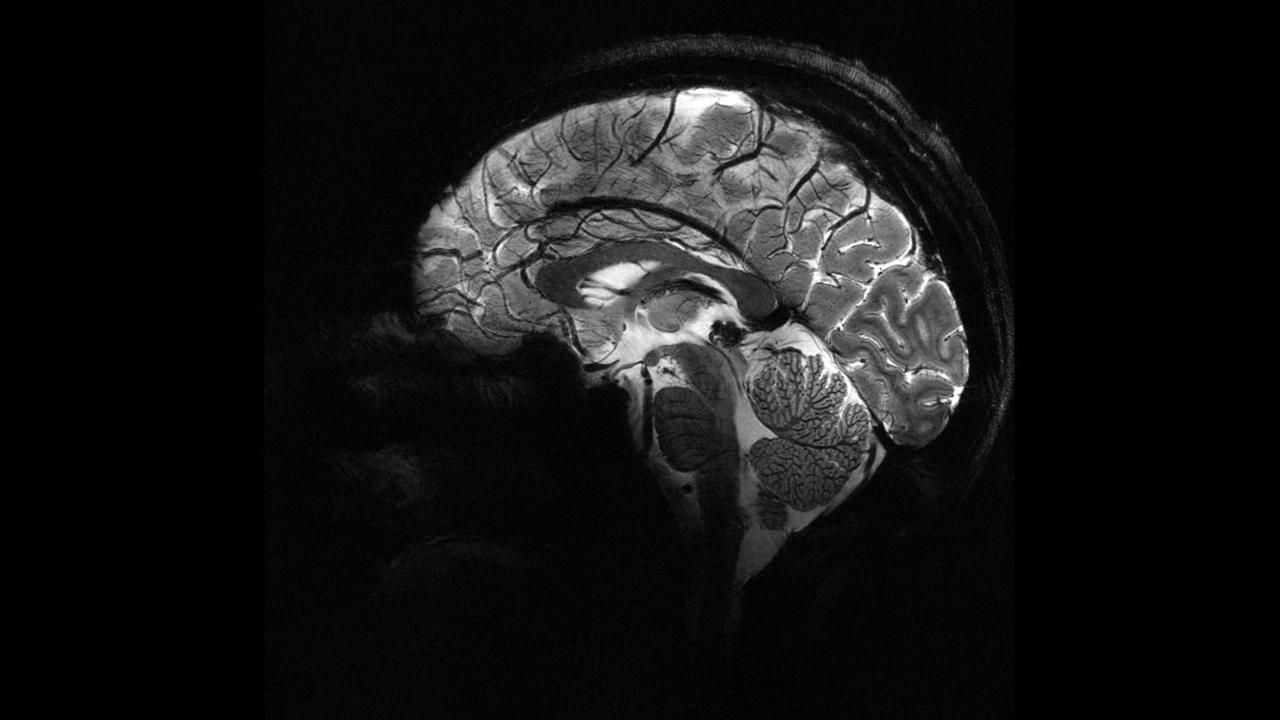

Epilepsiye farklı nedenler yol açsa da, vakaların yaklaşık yüzde 30’u beyindeki yapısal anormalliklerden kaynaklanıyor. Ancak bu lezyonlar, özellikle de beynin kıvrımlarının derinliklerinde saklı olan en küçük olanlar, çoğu zaman MR görüntülerinde fark edilmiyor.

Araştırmada kortikal displazi ve fokal epilepsi hastaları üzerinde testler yapıldı. Daha önce MR sonuçları “normal” raporlanan bu çocukların yüzde 80’inde aslında gizli lezyonlar olduğu belirlendi.

Yapay zekâ aracı hem MR hem de PET taramalarını analiz ettiğinde, bir test grubunda yüzde 94, diğerinde yüzde 91 başarı oranı yakaladı. İlk gruptaki 17 çocuktan 12’si beyin lezyonlarının çıkarılması için ameliyat edildi ve 11’i artık nöbetsiz yaşıyor.